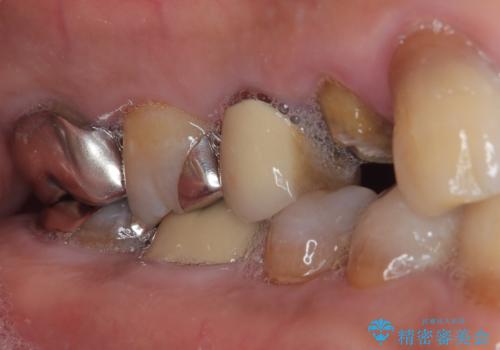

残存歯質の確認と感染リスクのチェック

ファイバーコアを築造・精密な支台歯形成と印象採得

オールセラミッククラウンの装着